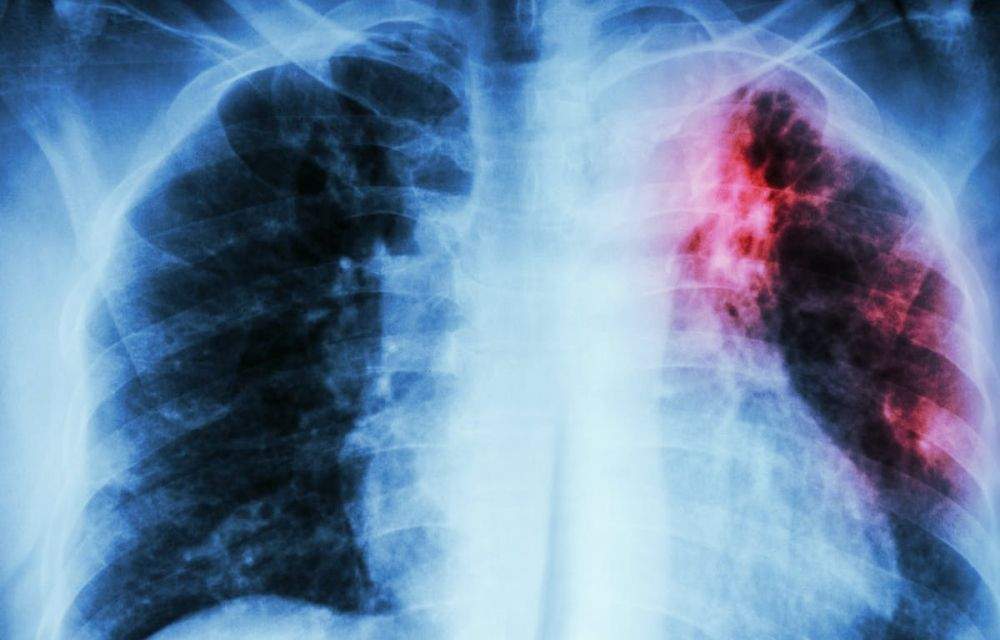

L’Organització Mundial de la Salut celebra aquest divendres el Dia mundial de la tuberculosi amb el lema “Sí podem posar fi a la tuberculosi”. El ministeri de Salut explica que durant el 2022 a través del Programa de prevenció i control va analitzant quatre sospites de la malaltia que s’han acabat confirmant. D’aquests, 1 correspon a un resident al país i 3 es van identificar al Servei d’Immigració. S’han detectat en homes d’entre 35 i 54 anys, així com s’ha fet un seguiment a sis contactes, dels quals 5 han estat dels casos detectats al Principat i un d’un cas d’Espanya amb una mitjana d’edat de 36 anys. S’han fet 11 proves de la tuberculina als contactes i en un cas ha donat positiu. Així mateix, s’ha fet una radiografia de tòrax.

La taxa d’incidència a Andorra anual es situa en 1,22 casos per cada 100.000 habitants. Si ens fixem en els darrers 25 anys, Salut va analitzar 218 sospites, de les quals 193 es van confirmar posteriorment. Concretament, 146 dels afectats eren residents al país i la taxa d’incidència en el darrer quinquenni és de 2,8, una dada és la segona més baixa dels darrers vint anys.